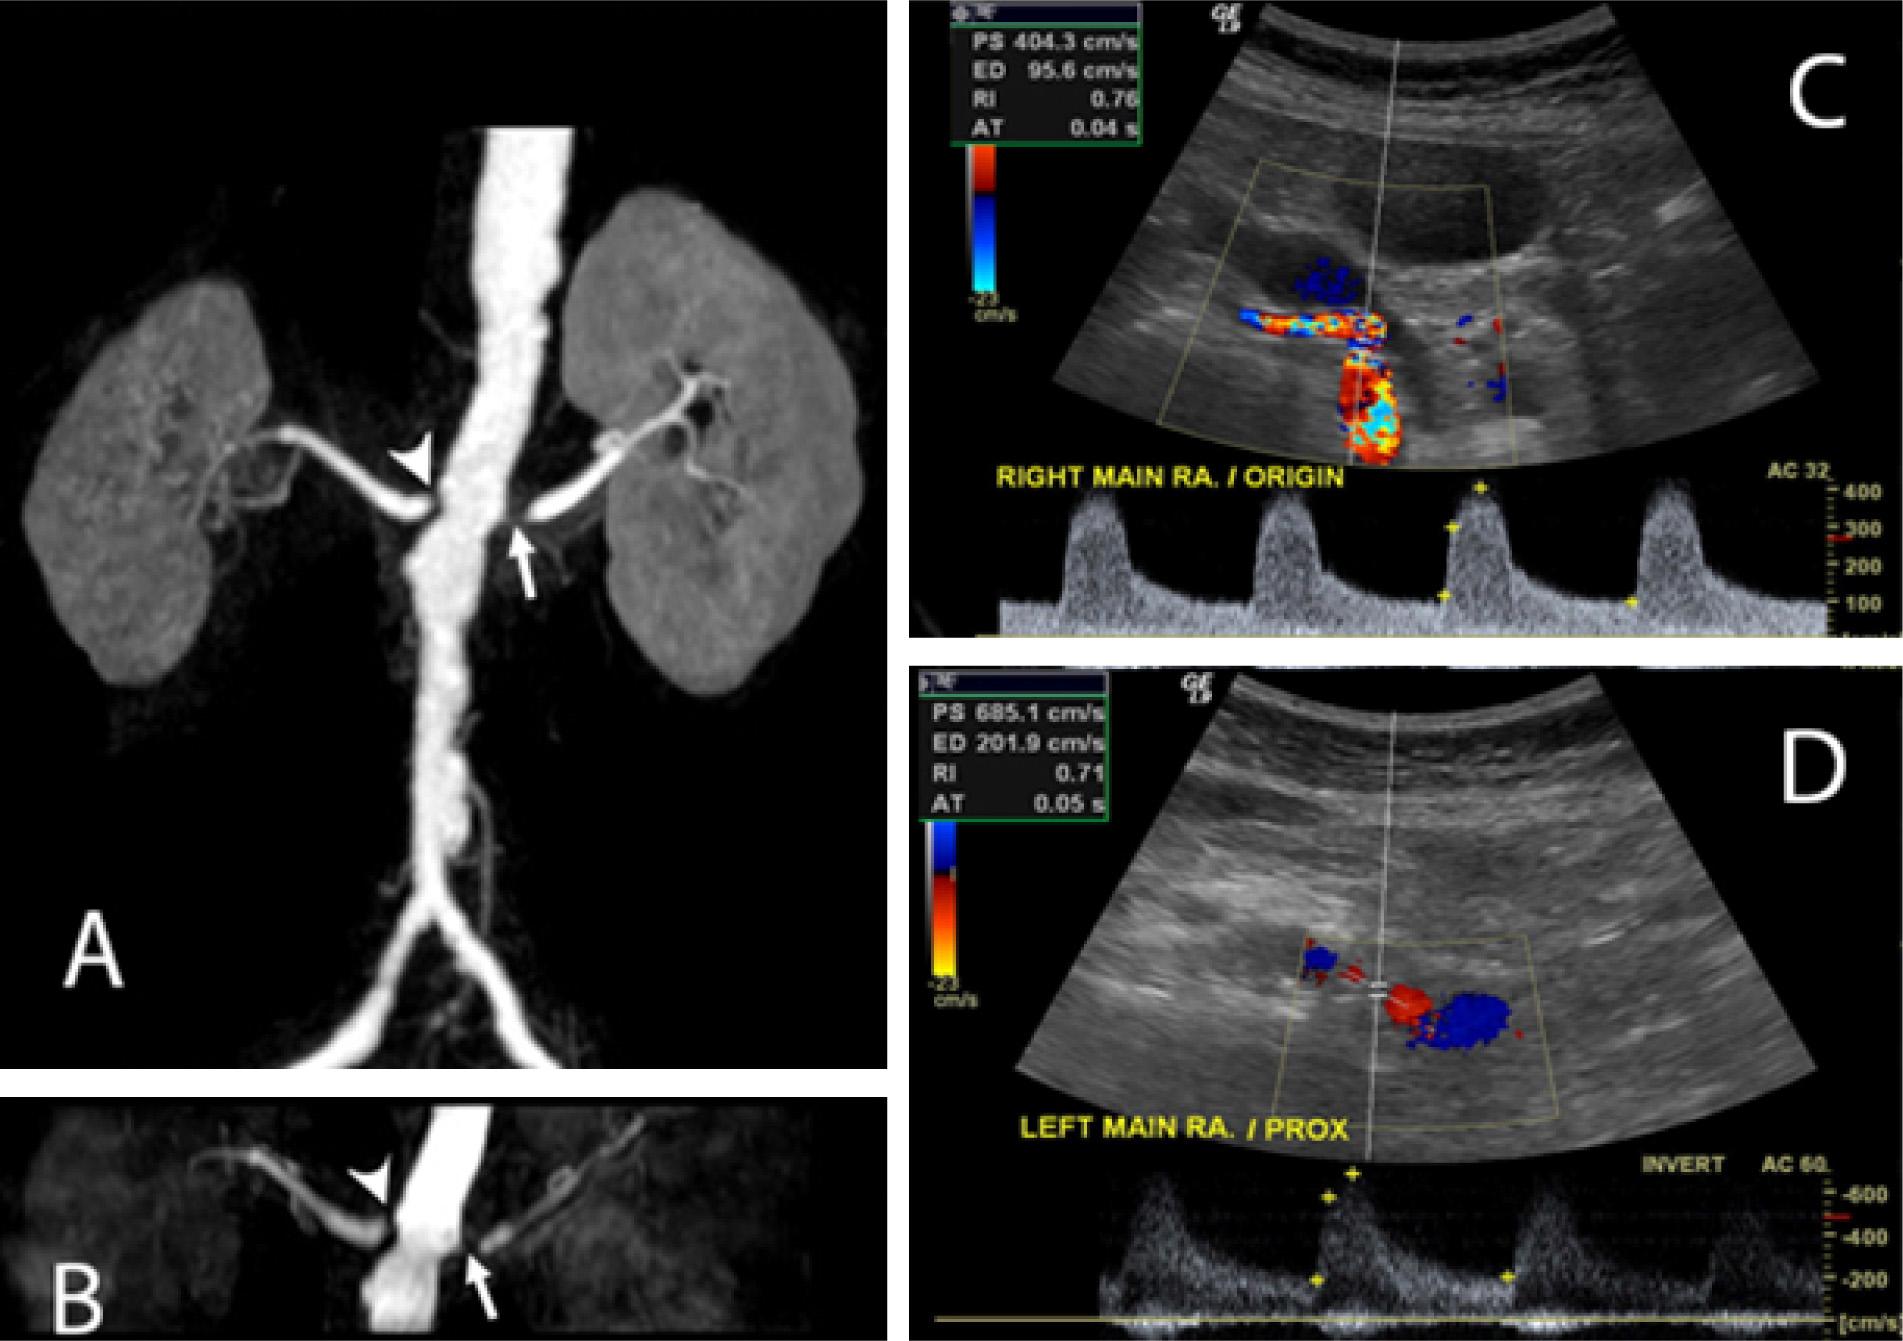

Figure 1

Color Doppler ultrasound and contrast-enhanced magnetic resonance angiography determination of the degree of renal artery stenosis per segment